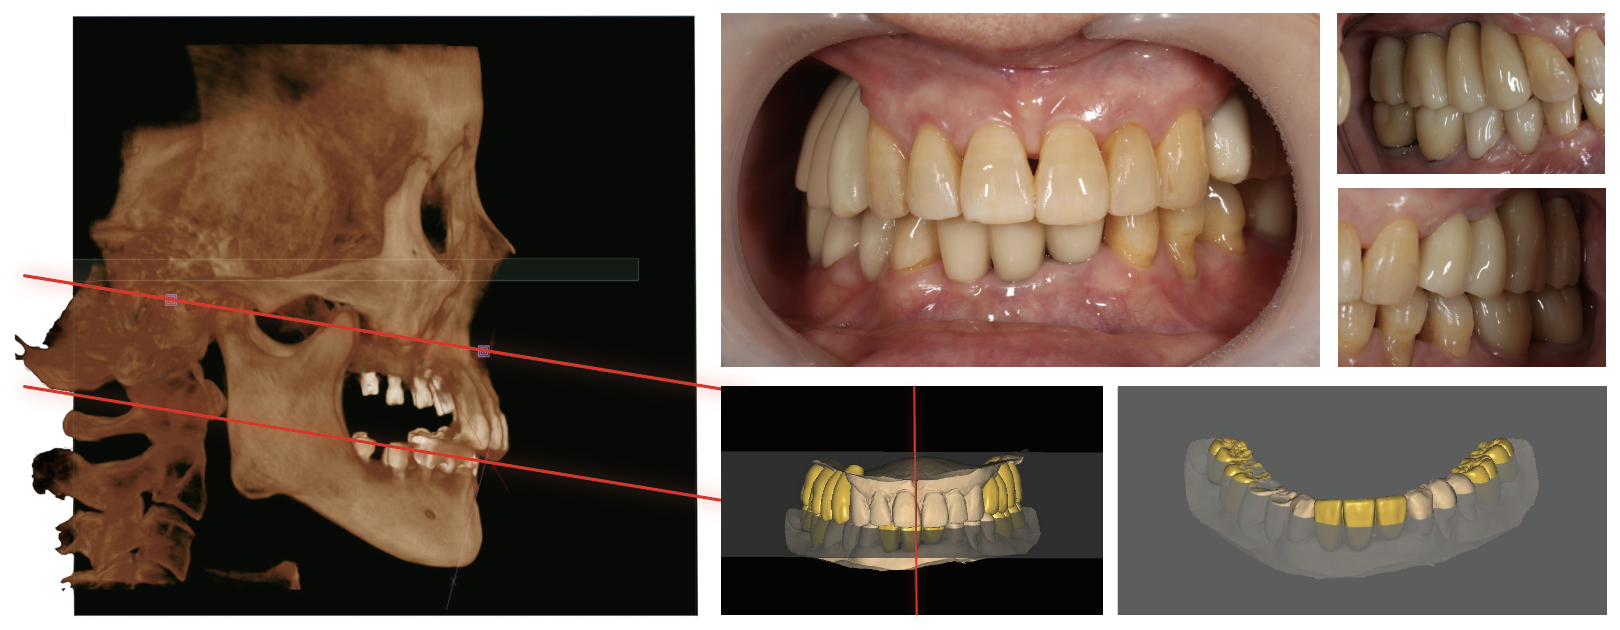

AI的增強(qiáng)在CBCT應(yīng)用

Dentium-AI自動(dòng)檢測掃描圖像上的位點(diǎn)進(jìn)行正畸分析。

AI咬合平面:有助于發(fā)現(xiàn)無牙頜患者的咬合面,作為參考。rainbow 3Dviewer附帶此功能,無需額外付費(fèi)。